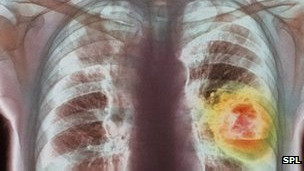

په برتانيا کې د بل هر سرطان په پرتله زيات خلک د سږو له سرطان نه مري.